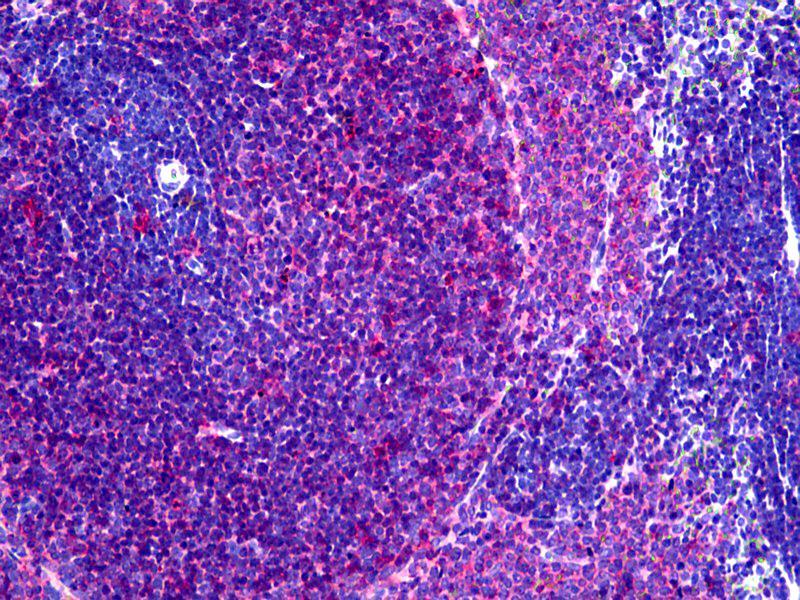

Flow Cytometry (FACS), Immunohistochemistry (Frozen Sections) (IHC (fro)), Immunohistochemistry (Paraffin-embedded Sections) (IHC (p)), Western Blotting (WB), Immunohistochemistry (IHC)

Recognizes a monomorphic determinant of the rat I-A antigen present on B lymphocytes, dendritic cells, some macrophages and certain epithelial cells. Reacts with certain mouse strains of MHC haplotypes k and s. Analysis of recombinant mouse strains showed that the determinants mapped to the I-A region. Does not react with the BDIX rat strain. Expression is polymorphic in mice. This product is routinely tested in flow cytometry on rat splenocytes.

Approved: Flo (1:50 - 1:100), IHC, IHC-Fr, IHC-P (10 μg/mL), WB

Usage: Flow Cytometry: Use 10 μL of the suggested working dilution to label 10^6 cells in 100 μL. Method sheets are available on request. Immunohistology: This product does not require antigen retrieval using heat treatment or protein digestion prior to staining of formalin-fixed paraffin-embedded sections, but results may be enhanced with heat treatment using 0.01M citrate buffer  pH 6.This clone has also been described reacting with paraffin-embedded material following PLP fixation (periodate-lysine-paraformaldehyde)